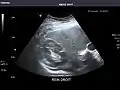

Right kidney

Kidneys: Right and left kidneys measure 11.5 cm and 12 cm in length respectively. No hydronephrosis. Small left lower pole kidney cyst.